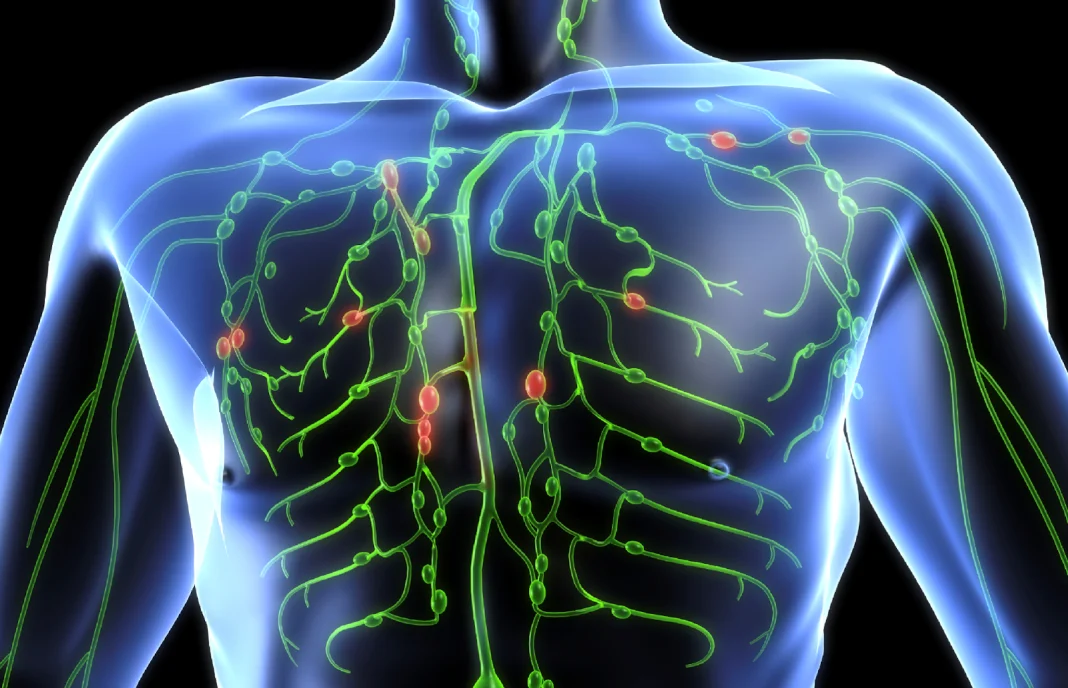

La finalidad del sistema linfático es transportar líquidos y células del sistema circulatorio a los tejidos del cuerpo. El sistema linfático ayuda a eliminar las toxinas del cuerpo, los desechos y las bacterias nocivas, y luego los envía al sistema circulatorio para ser eliminados por la orina y las heces. El sistema linfático juega un papel vital en la lucha contra enfermedades como la enfermedad de Lyme, el cáncer y otras enfermedades infecciosas.

La circulación linfática es el sistema circulatorio que permite que el sistema linfático se mueva y funcione adecuadamente. El líquido linfático circula a través de los vasos linfáticos, en los que hay vasos sanguíneos, y fue descrito por primera vez en el siglo XVII. Estos vasos contienen células y tejidos que componen el sistema inmunitario, así como células del sistema linfático. Los vasos linfáticos se conectan con los tejidos del cuerpo para permitir que el líquido linfático viaje libremente a través de los tejidos.

El líquido linfático se recolecta en las terminaciones de los vasos y es transportado a través de los vasos linfáticos a los ganglios linfáticos. Los ganglios linfáticos filtran el líquido en busca de entidades extrañas o patógenos que puedan estar presentes, como bacterias o virus. Si lo encuentra, crea células defensivas específicas de estas entidades, iniciando una respuesta inmune. El líquido también es purificado de desechos tóxicos y células muertas y luego regresado al flujo sanguíneo.